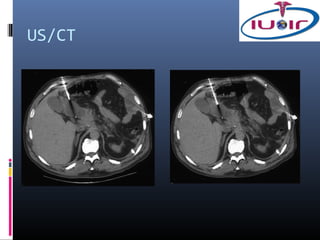

US/CT